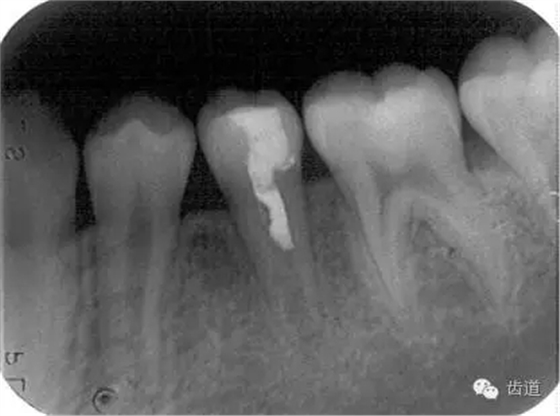

Apexification

Apexogenesis

術(shù)后三個(gè)月

術(shù)后六個(gè)月

術(shù)后兩年